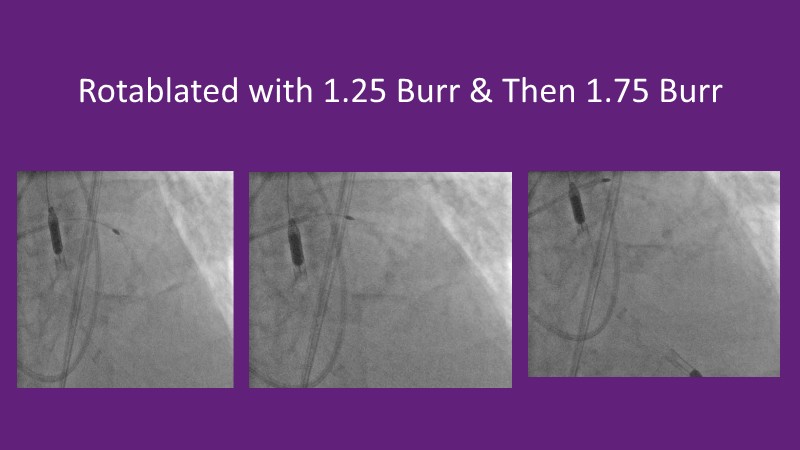

Recent data are discussed alongside insights from high-volume operators to show how calcium modification strategies are evolving and being integrated into contemporary PCI workflows.

By combining trial results, practical case experience, and emerging treatment algorithms, the discussion highlights how lesion preparation, procedural planning, and decision-making continue to improve in daily practice when managing complex calcified disease.